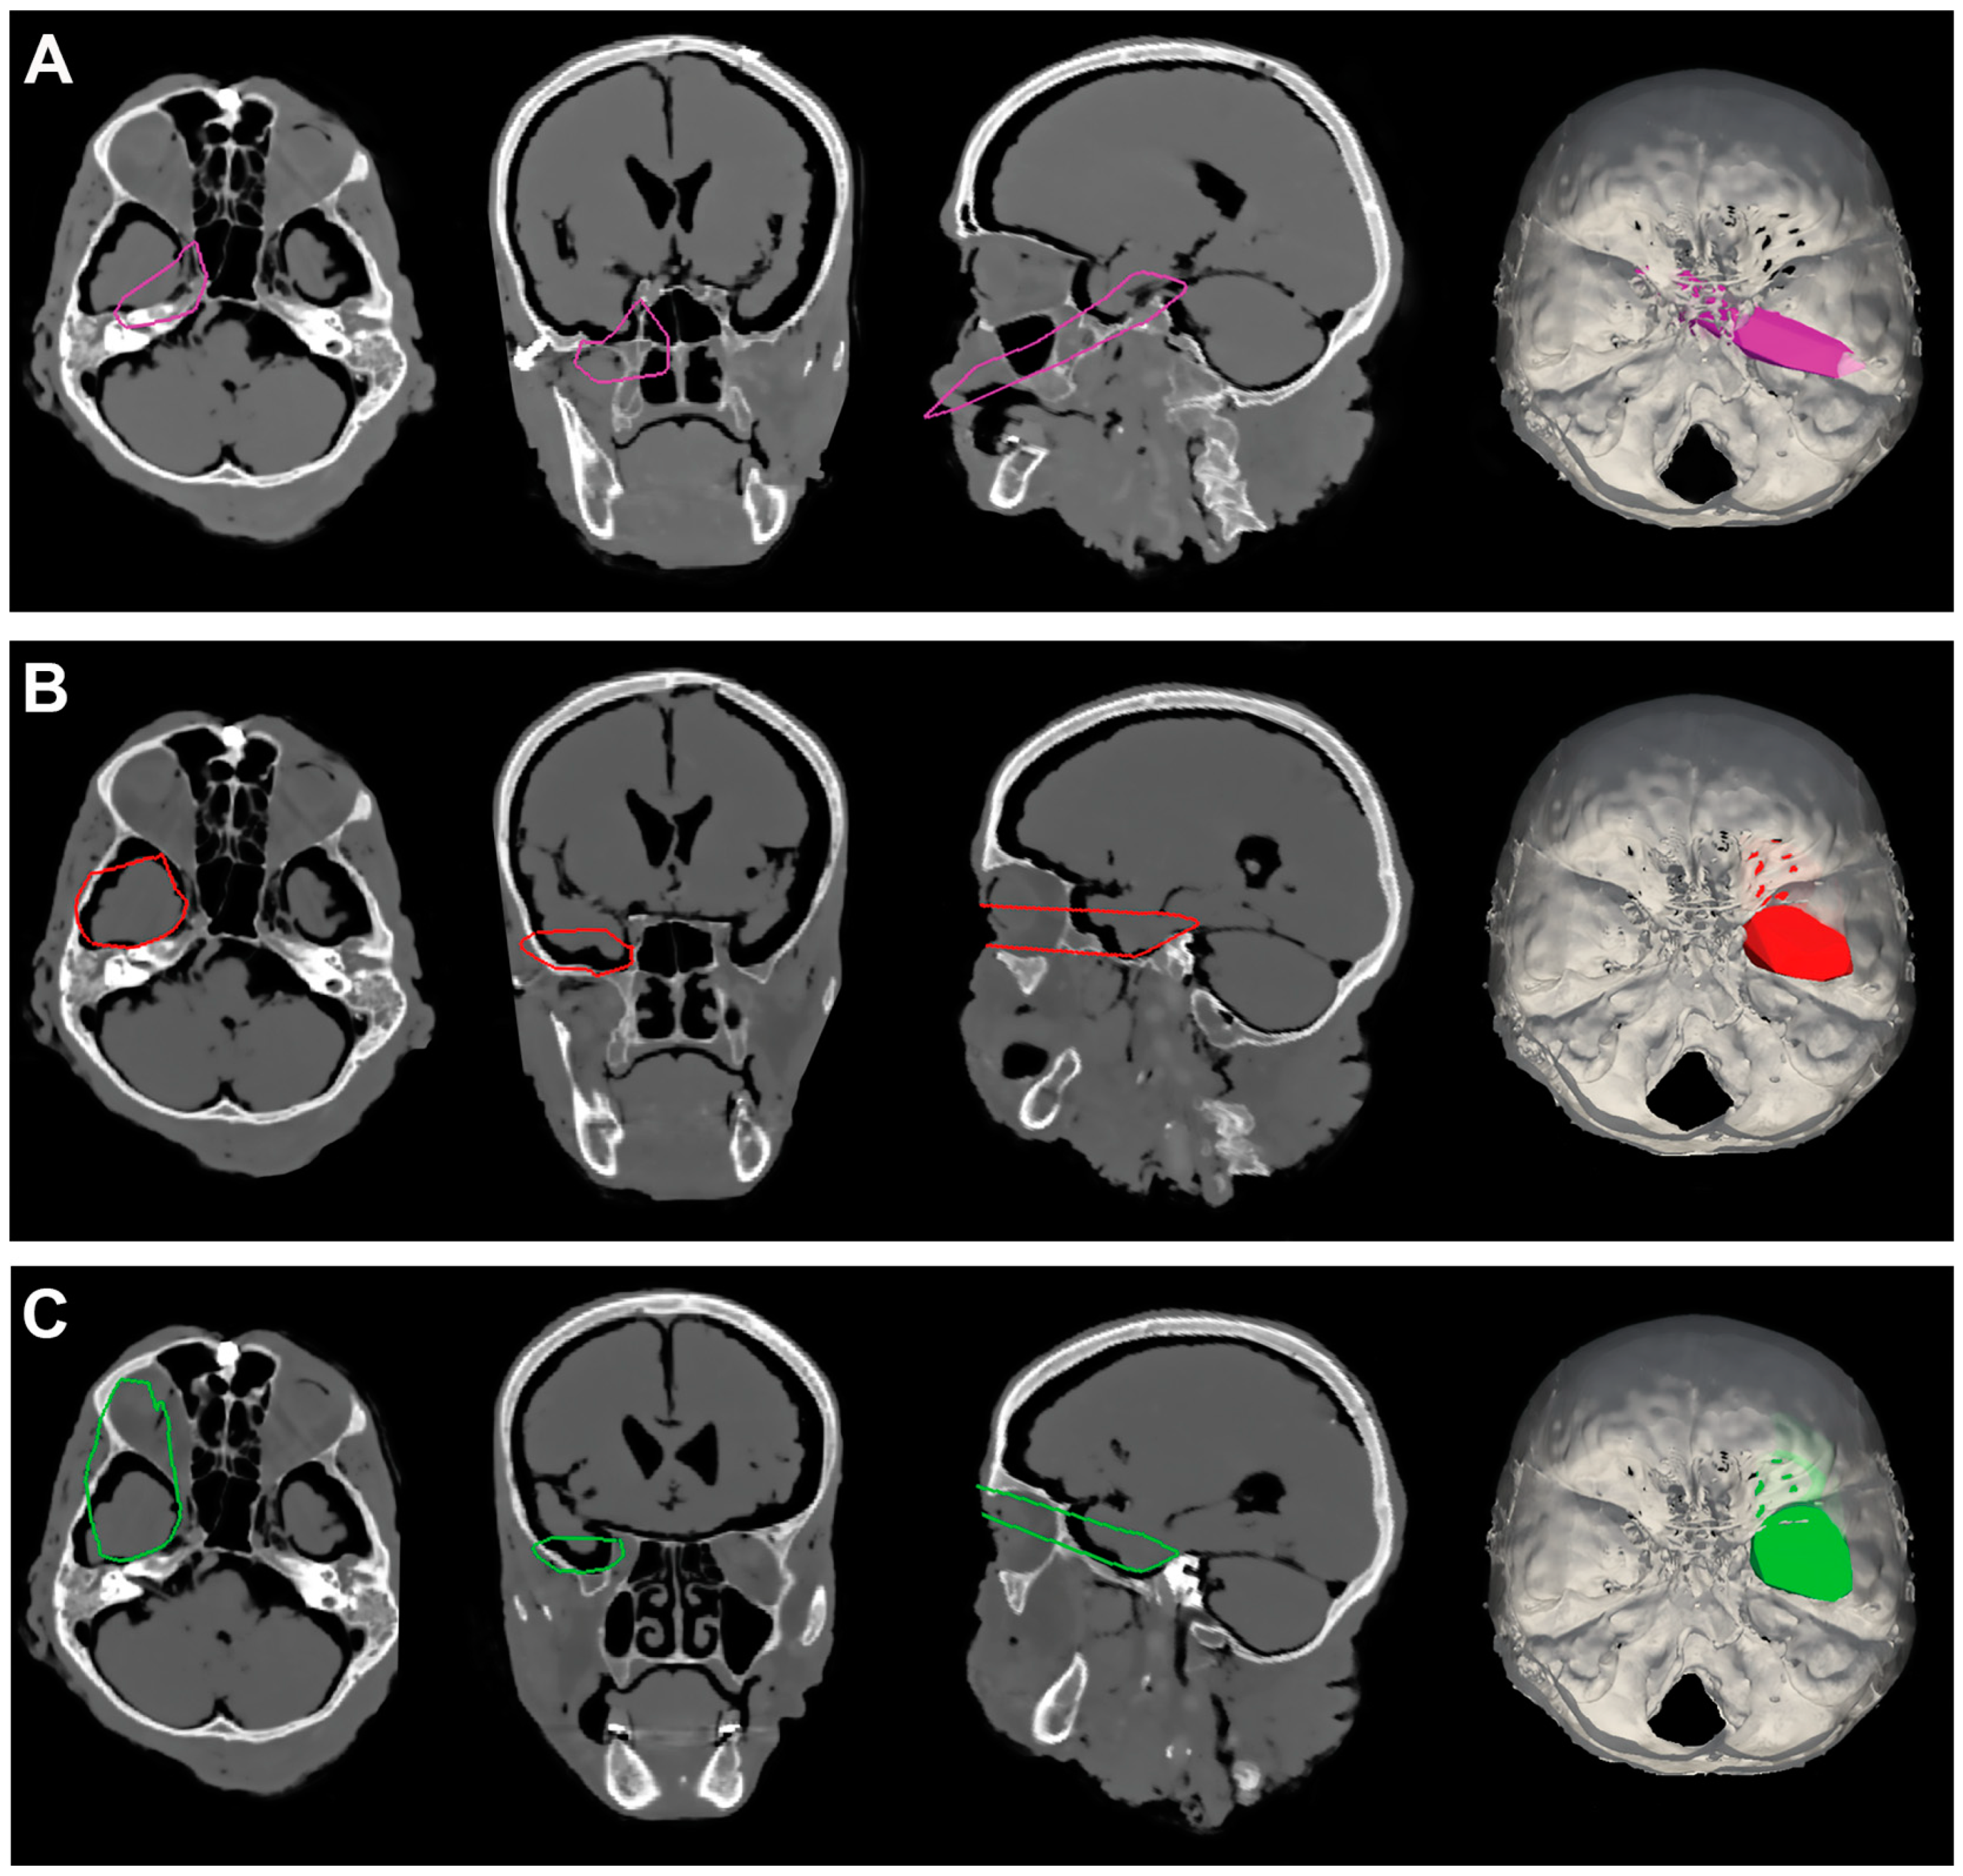

Meckel’s cave was divided into 8 surfaces, rendered with the ITK-SNAP software v. 4.0.2 from each CT scan (Figure 2). Dedicated software (Autodesk Meshmixer v. 3.5® and ApproachViewer v. 1), part of GTX-Eyes-II) quantified the percentage value of the exposed area by all approaches for each of the 8 surfaces [7].

Figure 2.

The 8 surfaces of Meckel’s cave that were rendered with ITK-SNAP software from CT scans. Red: trigeminal stem; green: Gasserian ganglion; orange: V1 medial; yellow: V1 lateral; light-blue: V2 medial; blue: V2 lateral; purple: V3 medial; violet: V3 lateral.